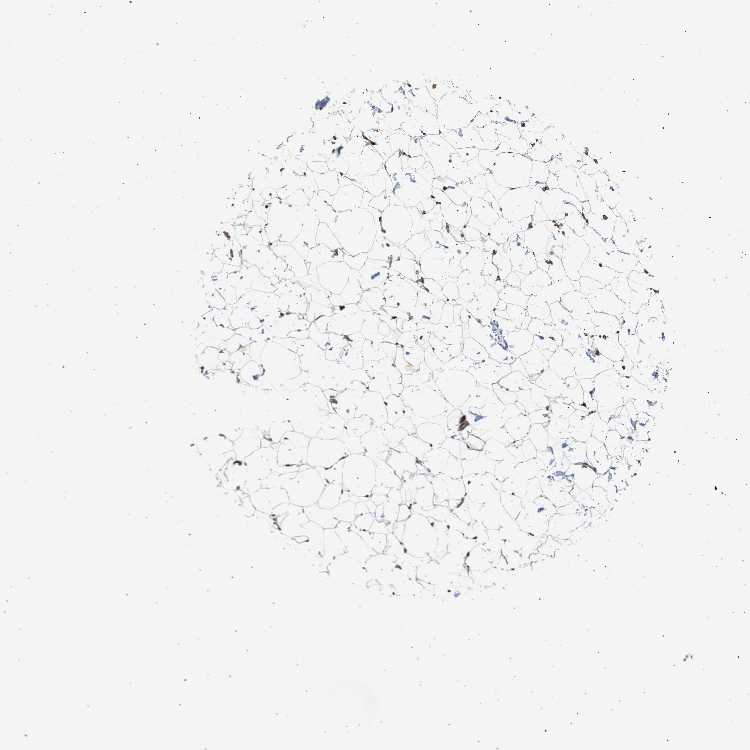

SOFT TISSUE 1 - Antibody stainingi

Antibody staining in the annotated cell types in the current human tissue is reported as not detected, low, medium, or high, based on conventional immunohistochemistry profiling in selected tissues. This score is based on the combination of the staining intensity and fraction of stained cells.

Each image is clickable and will lead to virtual microscopy that enables deeper exploration of all samples and also displays staining intensity scores, fraction scores and subcellular localization as well as patient and tissue information for each sample.